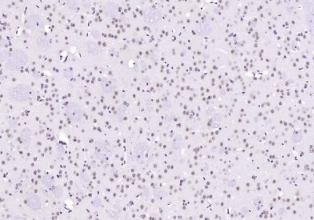

多聚甲醛固定,石蜡包埋(小鼠脑组织);用柠檬酸钠缓冲液(pH6.0)煮沸15min后获得抗原;用3%过氧化氢阻断内源性过氧化物酶20分钟;在37℃下封闭缓冲液(正常山羊血清)30min;用(Alpha B Crystallin)多克隆抗体进行抗体孵育。在4°C下1:400整晚,然后根据SP试剂盒(兔子)说明和DAB染色进行操作。